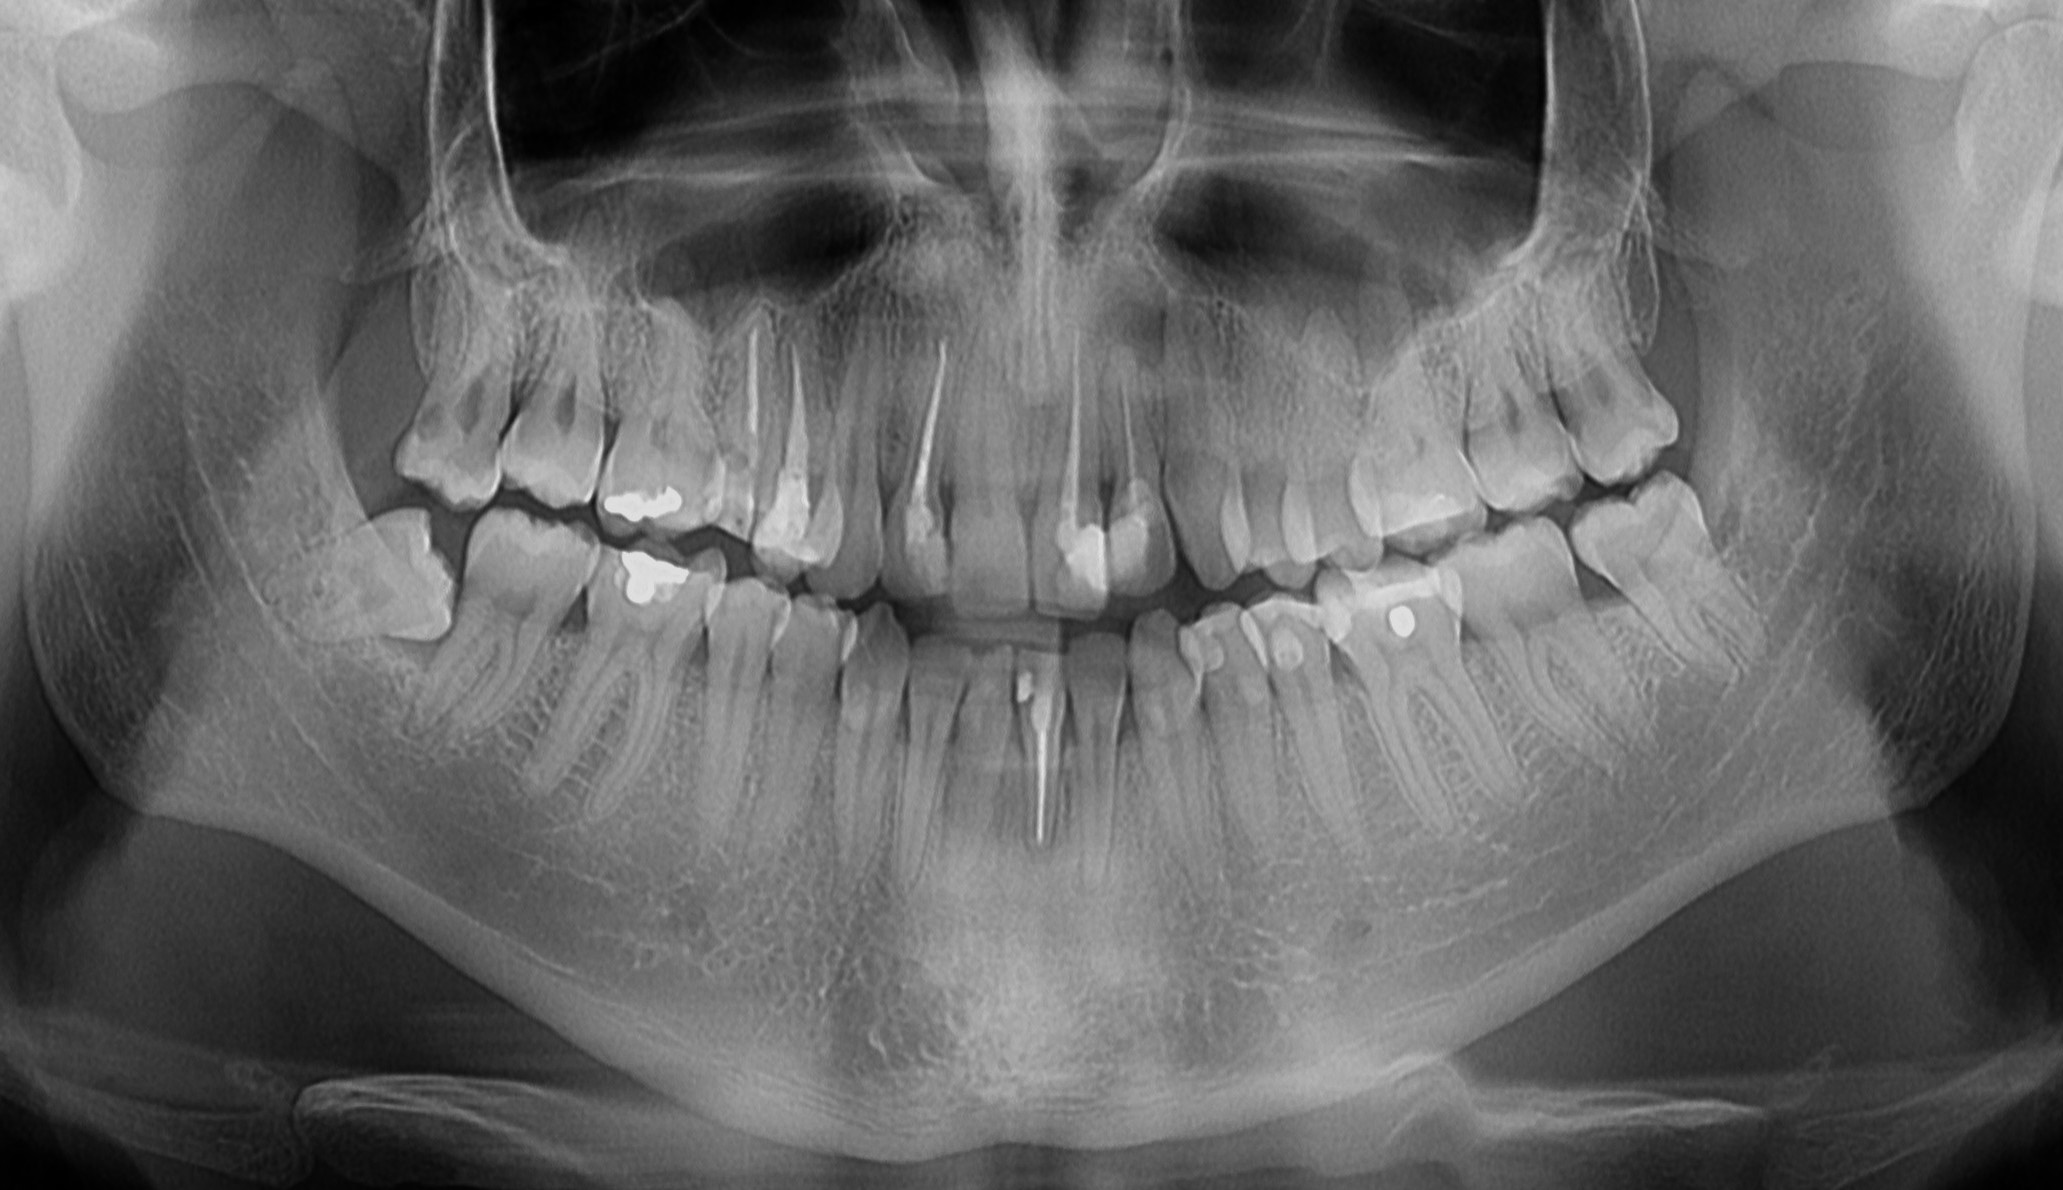

Ortopan-panoramski snimak zuba

Digitalni ortopan je snimak gornje i donje vilice, zuba i okolnih struktura.

Koristi se kao osnovni snimak u stomatološkoj dijagnostici, za planiranje stomatoloških terapija.

4 000,00 rsd